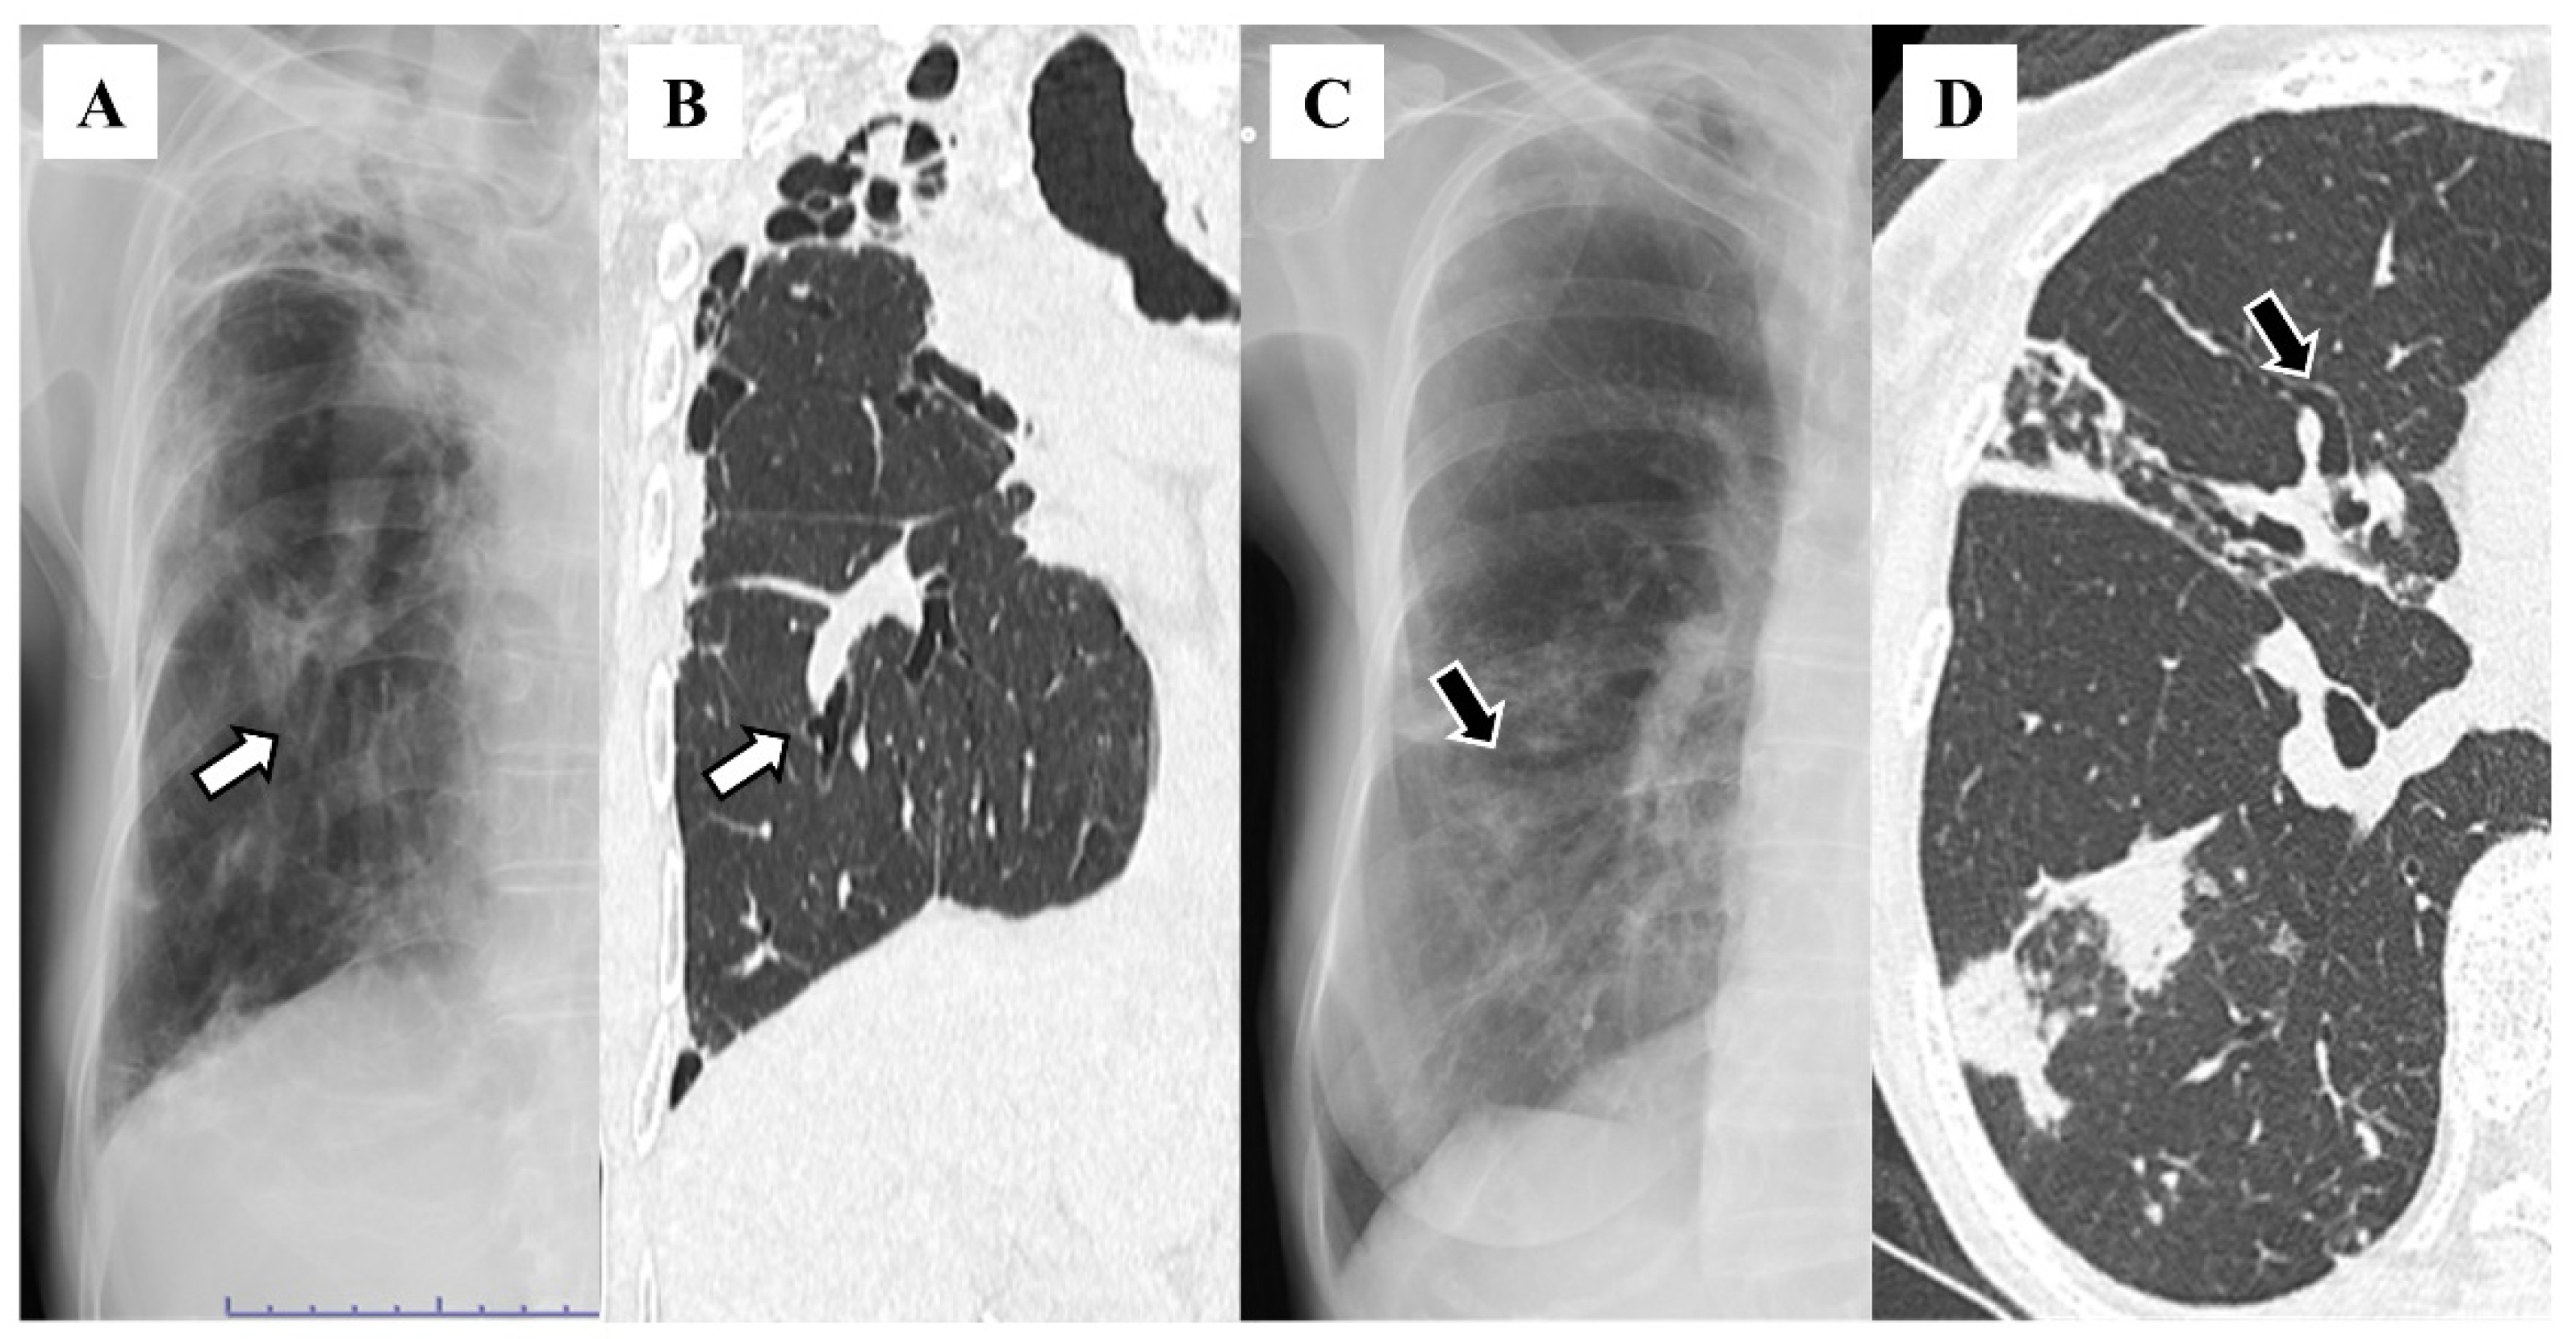

| Pleural thickening | 35 (26.9) |

| Vague diaphragm | 33 (25.4) |

| Lung volume loss | 15 (11.5) |

| Finger-in-glove sign | 12 (9.2) |